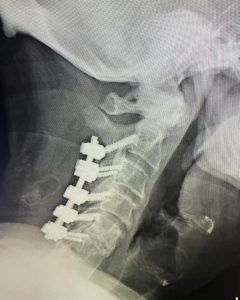

Here is a 64 y/o male who fell at home with resulting severe hand weakness and numbness due to cervical stenosis or narrowing of the spinal canal. The fall caused an injury to his spinal cord called myelopathy or a central cord syndrome. Central cord syndrome is a severe condition and can often result in permanent neurologic injury. Surgery (cervical laminectomy and fusion) was performed to relieve the pressure on the patient’s spinal cord and stabilize the spine. This patient responded very well to the surgery. In the days after surgery, he noted that his hands were stronger. By 6 weeks following surgery, he had recovered all of the normal function in his hands and arms.